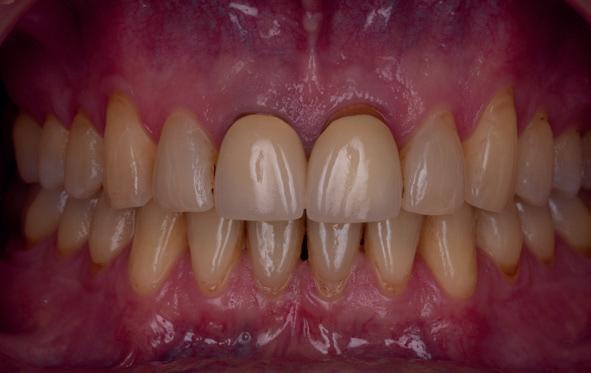

Esthetiek in de tandheelkunde, met name in het front, is een samenspel tussen de roze zachte weefsels en de witte harde weefsels. In het Engels wordt dit ook wel aangeduid met “pink and white esthetics”, waarbij het verkrijgen van correcte pink esthetics over het algemeen een grotere uitdaging vormt dan de white esthetics. Deze roze esthetiek is vooral van belang bij gebitselementen waarbij sprake is van recessie (het terugtrekken van de gingivalijn, waardoor de radix en een langere tand zichtbaar worden). De situatie wordt nog uitdagender wanneer een tand of kies niet is aangelegd, of in het verleden is verwijderd. Het element zorgt er immers voor dat de gingiva rondom de natuurlijke kroon ligt en dat er voldoende weefseldikte rondom deze kroon aanwezig is. Als het element ontbreekt, groeit het alveolaire bot dicht, omdat er geen radix meer is, en daarmee ook de mucosa (wanneer er geen element meer aanwezig is, spreken we niet meer van gingiva maar van mucosa), die dan afgevlakt is. De papillen tussen de afwezige elementen vlakken dan ook af.

Om één of meer afwezige elementen te herstellen bij een vaste voorziening, kan er een etsbrug of kunnen er implantaten worden geplaatst. De esthetiek valt of staat hierbij met de aanvulling van de zachte weefsels, zowel in de vorm van verbreding hiervan als het creëren van een zogenoemd emergence profile –dat wil zeggen dat de tand op een natuurlijk ogende wijze vanuit het tandvlees tevoorschijn moet komen.

Op 16-jarige leeftijd werd de patiënt door haar behandelend orthodontist naar de auteur verwezen voor een restauratieve oplossing voor de afwezige 11 en 21. In de tussenliggende periode had patiënt een retainer gedragen met twee kunststof tanden (afbeelding 1). Zowel de patiënt als haar moeder hadden een sterke voorkeur voor een implantaat gedragen vaste oplossing. Gezien haar jonge leeftijd was dit echter nog geen optie, omdat er nog verticale groei te verwachten viel. Implanteren op jonge leeftijd – dat wil zeggen vóór het 21e levensjaar – kan resulteren in een infrapositie van het implantaat, omdat de rest van het gebit nog verticaal kan doorgroeien.

Middels shared decision making werd het volgende plan overeengekomen: eerst zou er een etsbrug met vleugels op de 12 en 22 worden vervaardigd, om op 21-jarige leeftijd verder te gaan met implantologie.

18. Etsbrug frontbeeld

19. Etsbrug palatinaal